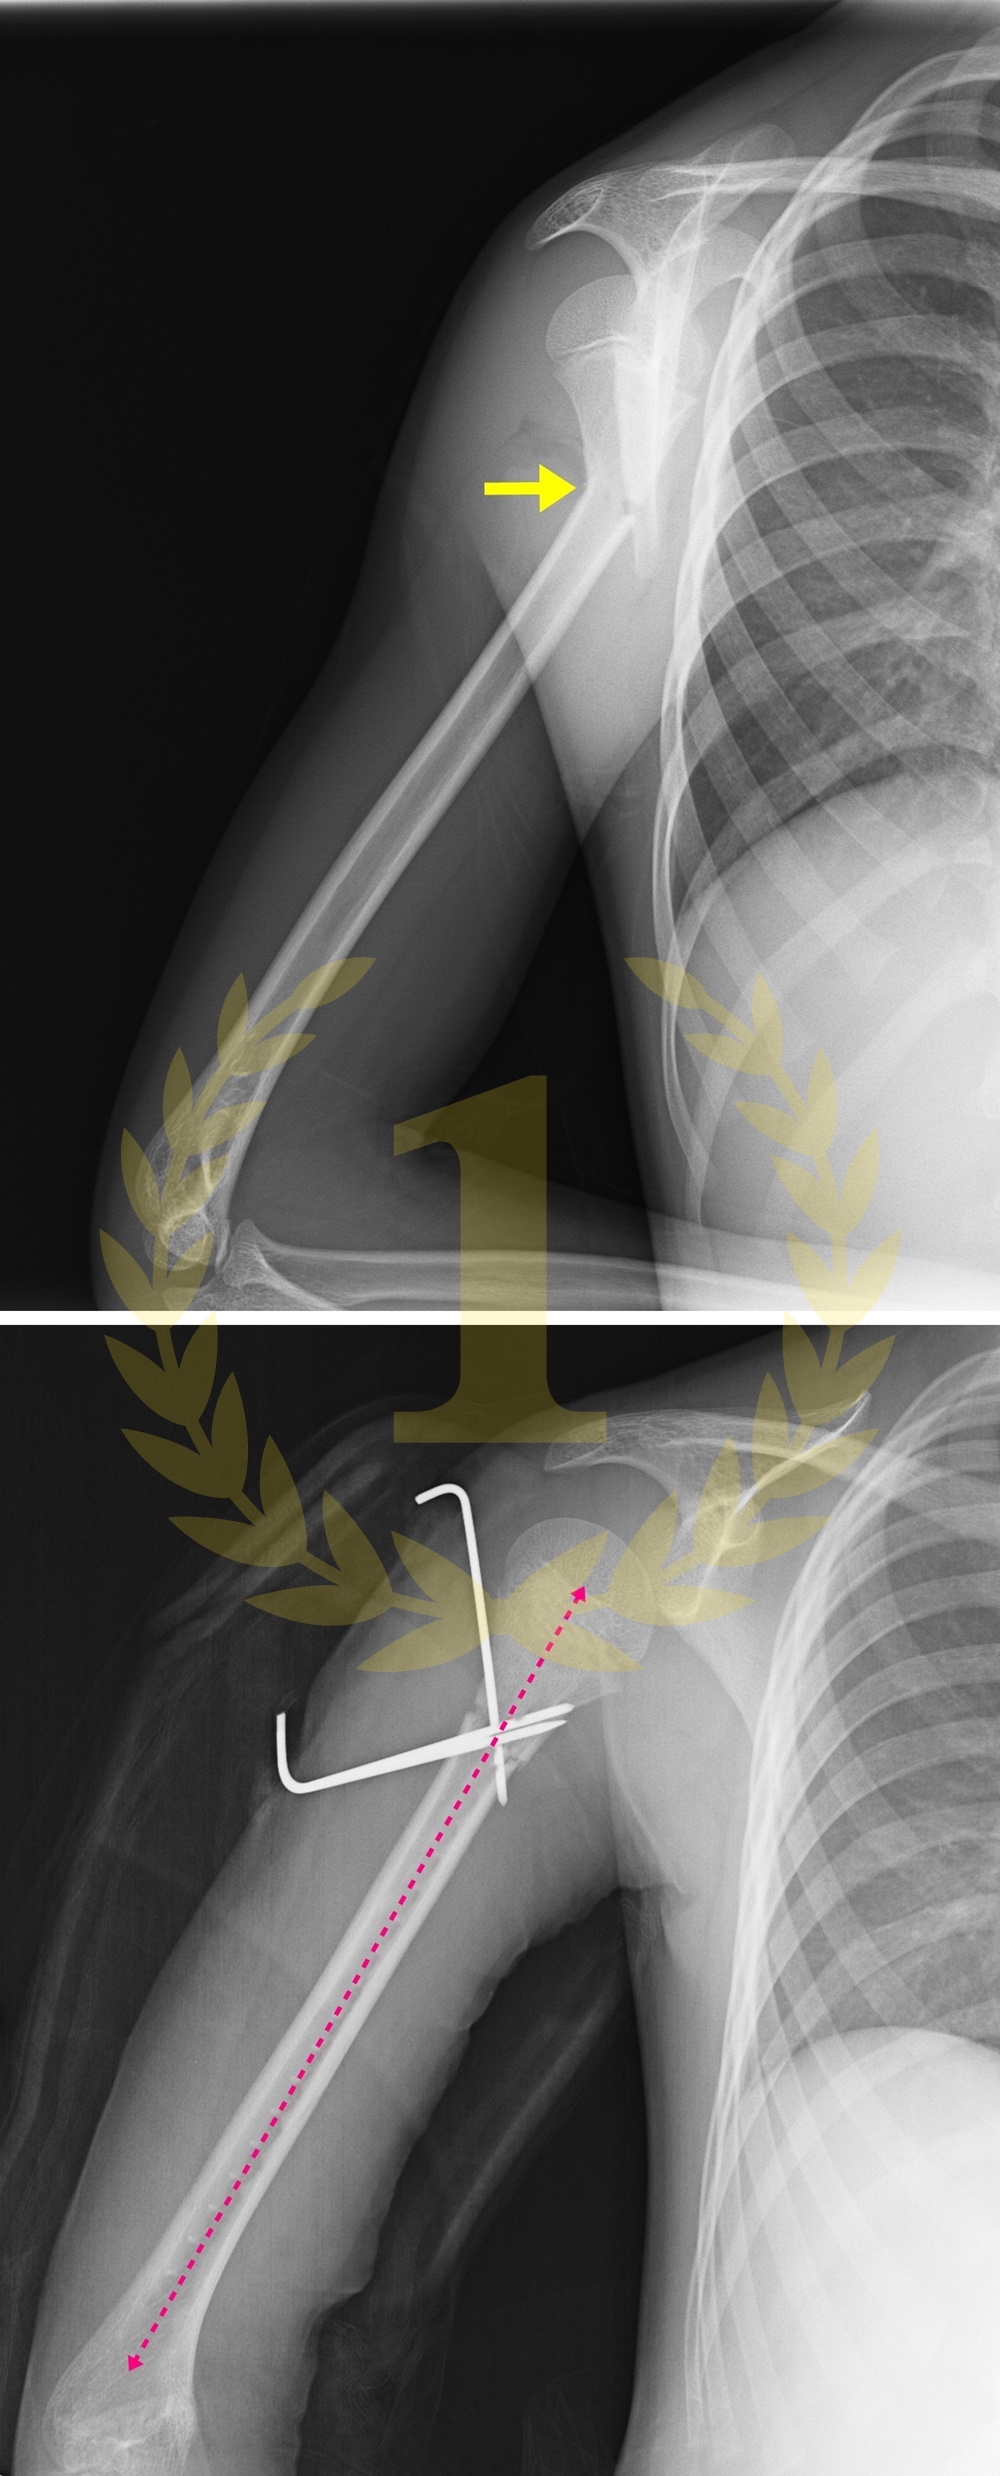

사지연장 및 변형교정

키수술ㅣ휜팔다리ㅣ휜손발가락ㅣ단지증ㅣ장지증